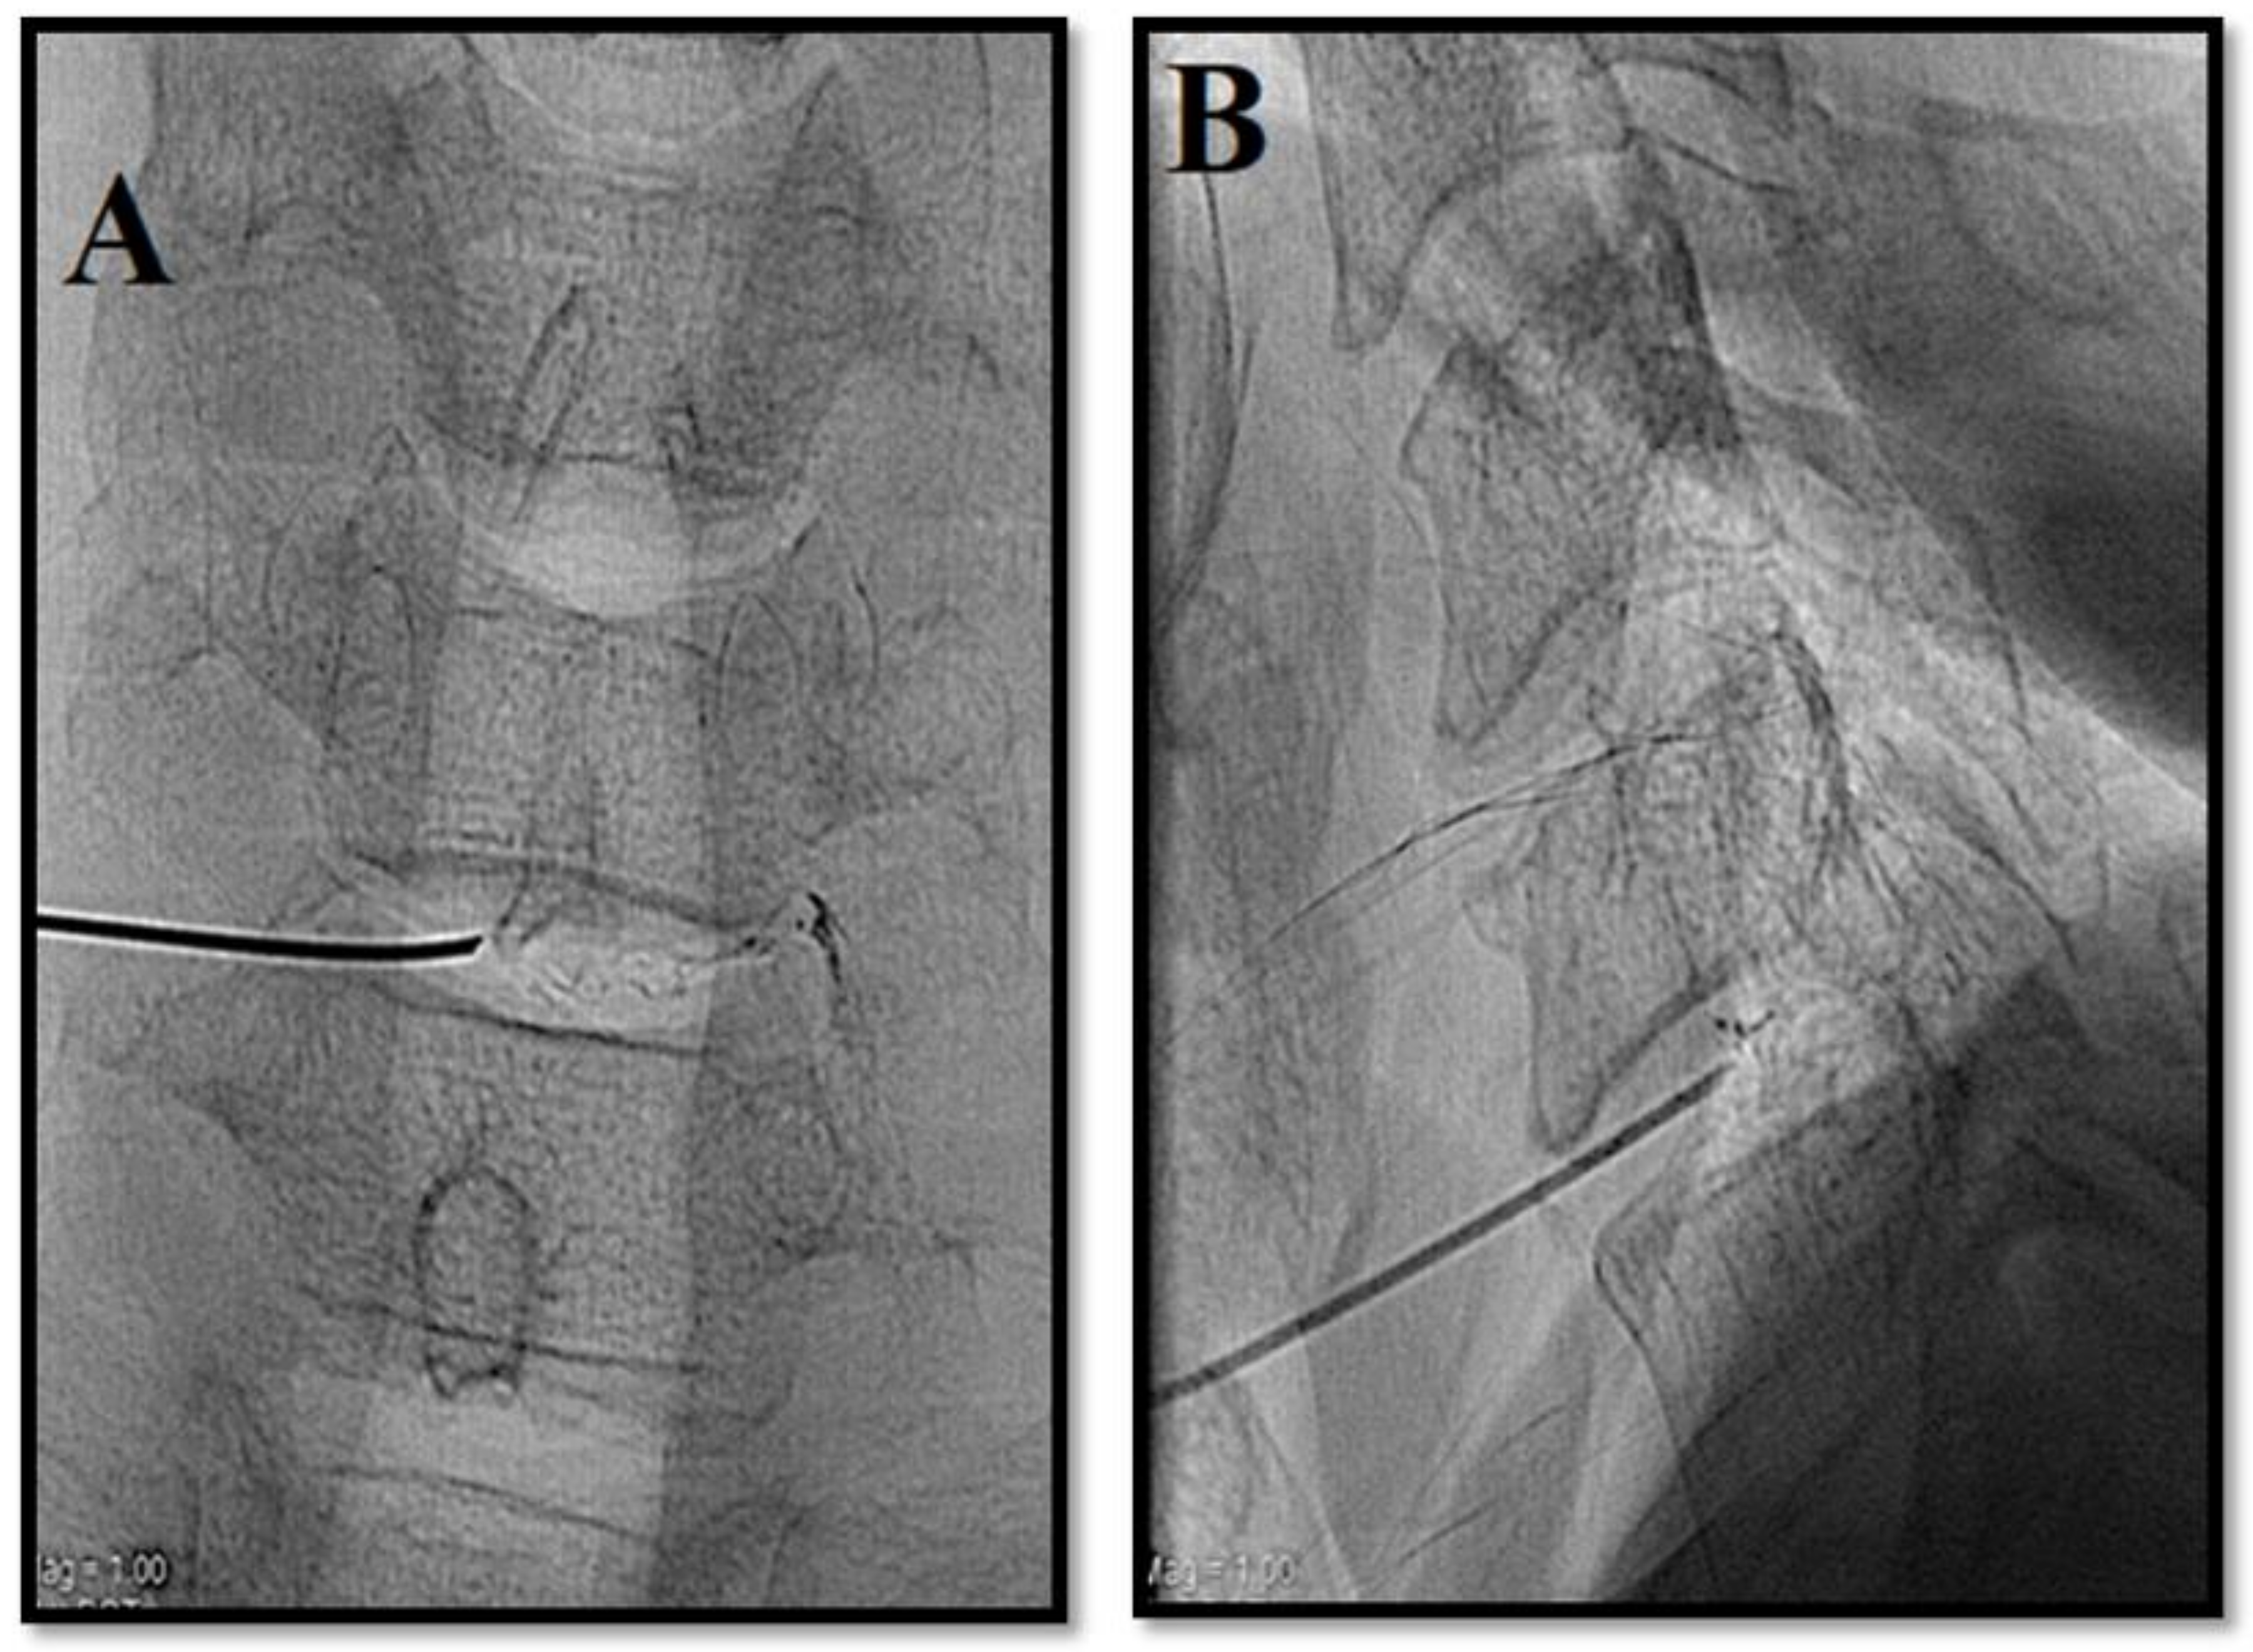

- Kelekis, A.; Filippiadis, D. Percutaneous treatment of cervical and lumbar herniated disc. Eur. J. Radiol. 2015, 84, 771–776. [Google Scholar] [CrossRef]

- Amoretti, N.; Huwart, L.; Marcy, P.Y.; Foti, P.; Hauger, O.; Boileau, P. CT-and fluoroscopy guided percutaneous discectomy for lumbar radiculopathy related to disc herniation: A comparative prospective study comparing lateral to medial herniated discs. Skelet. Radiol. 2013, 42, 49–53. [Google Scholar] [CrossRef]

- Gangi, A.; Tsoumakidou, G.; Buy, X.; Cabral, J.; Garnon, J. Percutaneous techniques for cervical pain of discal origin. Semin. Musculoskelet. Radiol. 2011, 15, 172–180. [Google Scholar] [CrossRef]